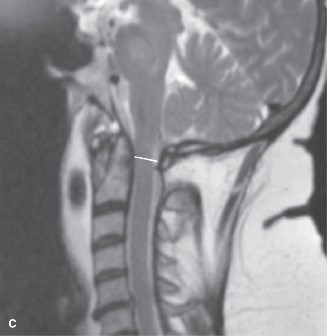

CASE 1 A 63-year-old male sustained a hyperextension injury to his neck while diving into a pool. Upon presentation, he reports decreased sensation in his hands and decreased strength in his arms and wrists, but no lower extremity complaints. On motor examination, he has 5/5 strength in his deltoids and elbow flexors and 4/5 strength in the elbow extensors, wrist extensors, and finger flexors. Lower extremity motor examination is normal. Sensation is decreased to light touch in both hands. Otherwise his sensation is preserved. Images of his cervical spine are shown in Figures 1–1 to 1–3.

Figure 1–3

The correct answer is (B). The clinical scenario describes a patient with central cord syndrome (CCS). CCS continues to be the most common incomplete spinal cord injury accounting for 15.7% to 25% of all spinal cord injuries. The characteristic presentation is an extension moment injury in a previously spondylotic and stenotic spine. Figures 1–1 to 1–3 demonstrate a spondylotic spine with central narrowing and CSF effacement that is worst at the C3–4 level. Bleeding, edema, and/or Wallerian degeneration lead to damage of the lateral corticospinal tract which is the main descending motor tract in the spinal cord. The more central anatomic position of the homunculus to the upper extremities places them at greater risk than those to the lower extremities. As such, injury to the lateral corticospinal tract is characterized by upper more than lower extremity involvement and motor deficits being more pronounced than sensory deficits.